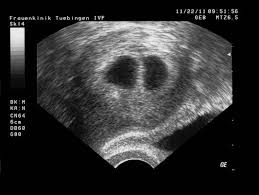

Huhuheute berichte ich euch von der 7 und der 8 WocheSo langsam fangen die Schwangerschaft Symptome an ich war in der 7 Woche zum ersten mal beim Frauenar. Frühe Zwillingsschwangerschaften im Ultraschall Eineiige Zwillinge in der 55 Schwangerschaftswoche. Wie funktioniert ein Ultraschall bei Zwillingen in der 5.

Frühe Zwillingsschwangerschaften im Ultraschall Eineiige Zwillinge in der 55 Schwangerschaftswoche. SSW ist Deine Gebärmutter so groß wie eine Faust. SSW - Ultraschall in der Schwangerschaft.

In dieser Fruchthöhle finden sich gelegentlich bereits kleine weißliche Flecken die durch die embryonalen Strukturen hervorgerufen werden. Woche SSW5 Alter 3 Wochen. In der Regel werden Zwillinge bereits bei der ersten Ultraschalluntersuchung entdeckt die etwa in der sechsten Schwangerschaftswoche erfolgt.